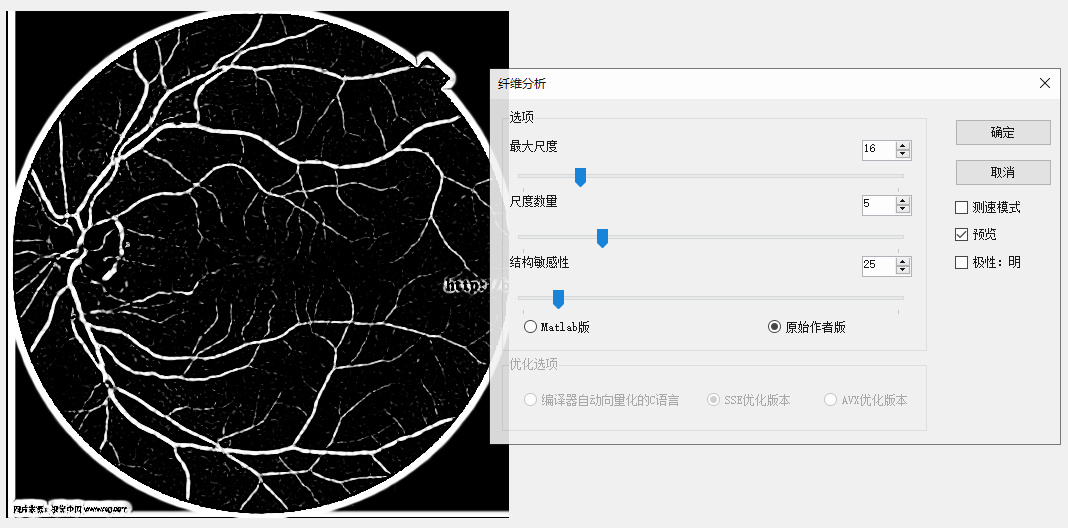

那一副醫學圖像做測試,效果確實不錯:

原圖 尺度數量為5,最大尺度為16的結果

同樣參數原始作者版本的結果,明顯沒有maltab的清晰